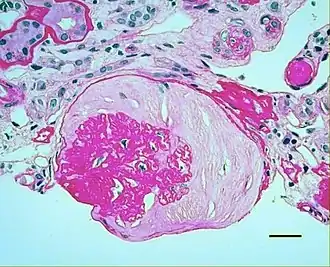

Micrograph showing renal arterial hyalinosis – pink ring right-of-centre. PAS stain.

In the kidneys, as a result of benign arterial hypertension, hyaline (pink, amorphous, homogeneous material) accumulates in the walls of small arteries and arterioles, producing the thickening of their walls and the narrowing of the arterial openings, a process known as arteriolosclerosis. The resulting inadequate blood flow produces tubular atrophy, interstitial fibrosis, and glomerular alterations (smaller glomeruli with different degrees of hyalinization – from mild to sclerosis of glomeruli) and scarring around the glomeruli (periglomerular fibrosis). In advanced stages, kidney failure will occur. Functional nephrons[6] have dilated tubules, often with hyaline casts in the opening of the tubules. Additional complications often associated with hypertensive nephropathy include glomerular damage resulting in protein and blood in the urine.

Histology

In benign nephrosclerosis, the changes occurring are gradual and progressive, however, there can be sufficient kidney reserve capacity to maintain adequate kidney function for many years.[10] The large renal arteries exhibit intimal thickening, medial hypertrophy, duplication of the elastic layer. The changes in small arterioles include hyaline arteriolosclerosis (deposition of hyaline, collagenous material), which causes glomerular collapse (wrinkling and thickening of capillary basement membranes and collapse of capillary lumen) and solidification (glomeruli exhibit sclerosis and increase in mesangial matrix). The degree of scarring correlates with the degree of glomerular filtration deficit.